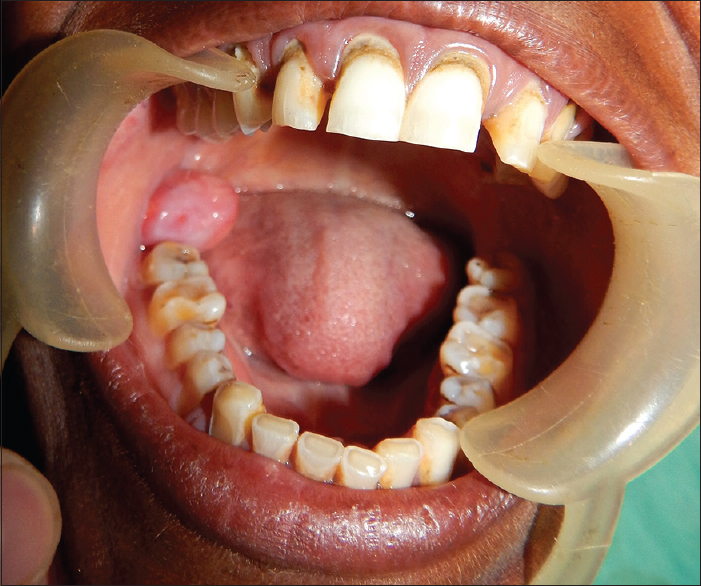

• The retromolar trigone (RMT) is a small triangular shaped subsite of the oral cavity:

• It is the portion of mucosa that lies behind the third inferior molar tooth covering the anterior ramus of the mandible.

• The base of the triangle is posterior to the last inferior molar tooth.

• The apex is in continuity with the tuberosity of the maxilla behind the last upper molar tooth.

• It is bounded laterally by the gingival buccal sulcus and medially by the anterior tonsillar pillar.